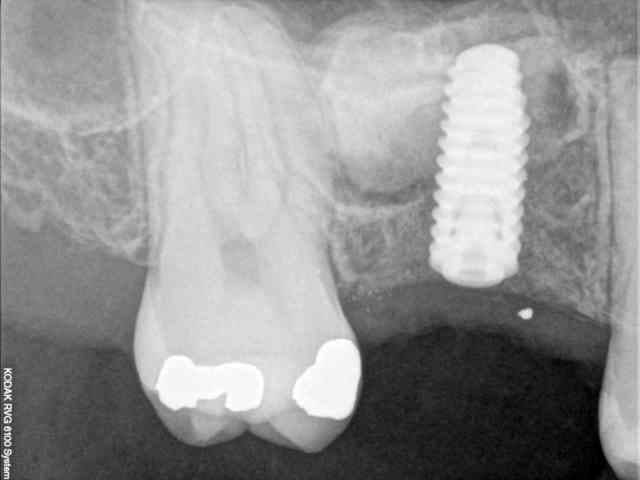

quasiment 6 mois entre les deux interventions (sinus lift et mise à jour)

c'est surtout la qualité des trabéculations osseuses qui m'interpelle.

d'habitude, on voit toujours un peu de particules, ici, c'est vraiment top.

une toute petite remarque, le point blanc sur la radio avec pilier de cicatrisation.

tu as raison, mais on le voit dés les premières radios post extraction.

j'en déduis donc que j'ai bossé comme un cochon pendant cet acte et qu'une inclusion (amalgame ?) est restée dans la gencive.

je crois que c'est la première fois que je vois une cliché radio à quelques mois post-op avec ce matériau et le résultat semble excellent.